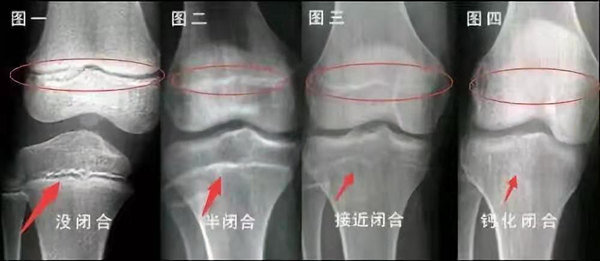

未成年時隨著年齡的增加骺軟骨端不斷骨化,骨骼就不斷增長。當骨骺線完全閉合時骨骼就停止生長,個子也就不再增長了。一般骨骺端完全閉合的年齡是18~20歲左右。

青少年一般什么時候骨骺閉合?

一般女孩是在16歲,男孩是在18歲。

一般來說,女孩的骨齡超過14歲,男孩的骨齡超過16歲,這時其骨骺線已接近閉合,基本沒有長高的機會了。

因此,越早了解骨骺線閉合情況,越早干預,孩子長高的可能性越大。